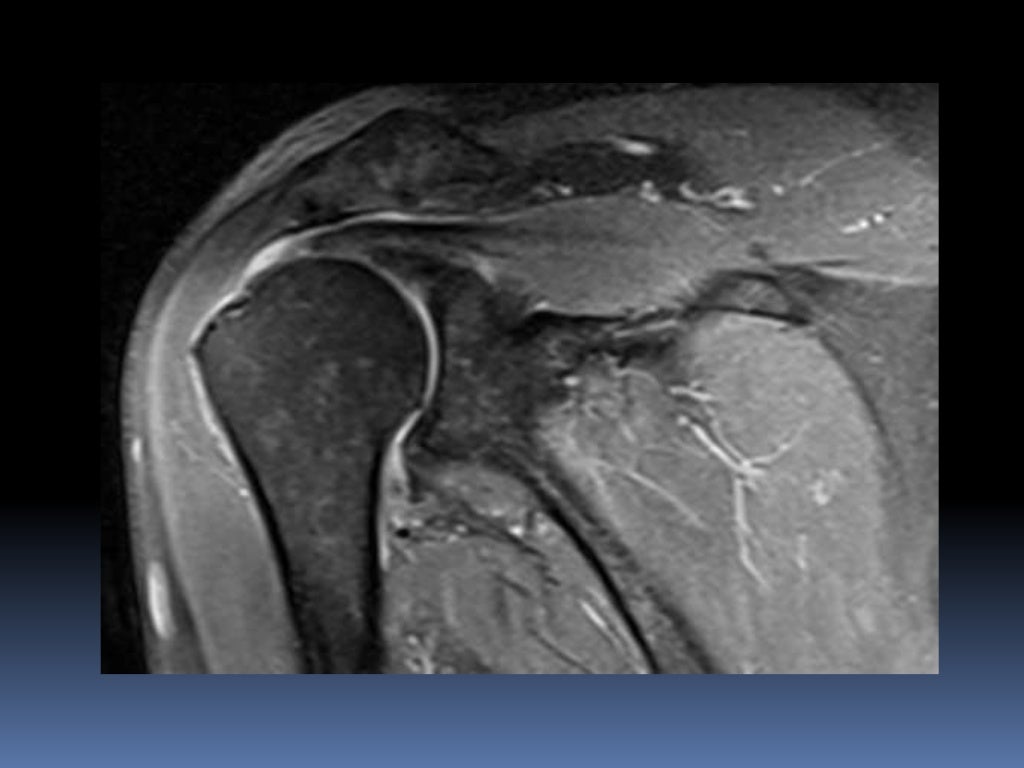

MRI Shoulder Musculoskeletal Imaging

MRI AP shoulder. Unidad Especializada en Ortopedia y Traumatologia en What Is A Shoulder Mri Mri of the shoulder provides detailed images of structures within the shoulder joint, including bones, tendons,. Magnetic resonance imaging (mri) is a critical diagnostic tool used to assess shoulder injuries and conditions. The mri allows accurate assessment of any pathologic changes of the structures of the shoulder, including the glenoid labrum, the humeral head, the articular. However, the technical jargon. What Is A Shoulder Mri.